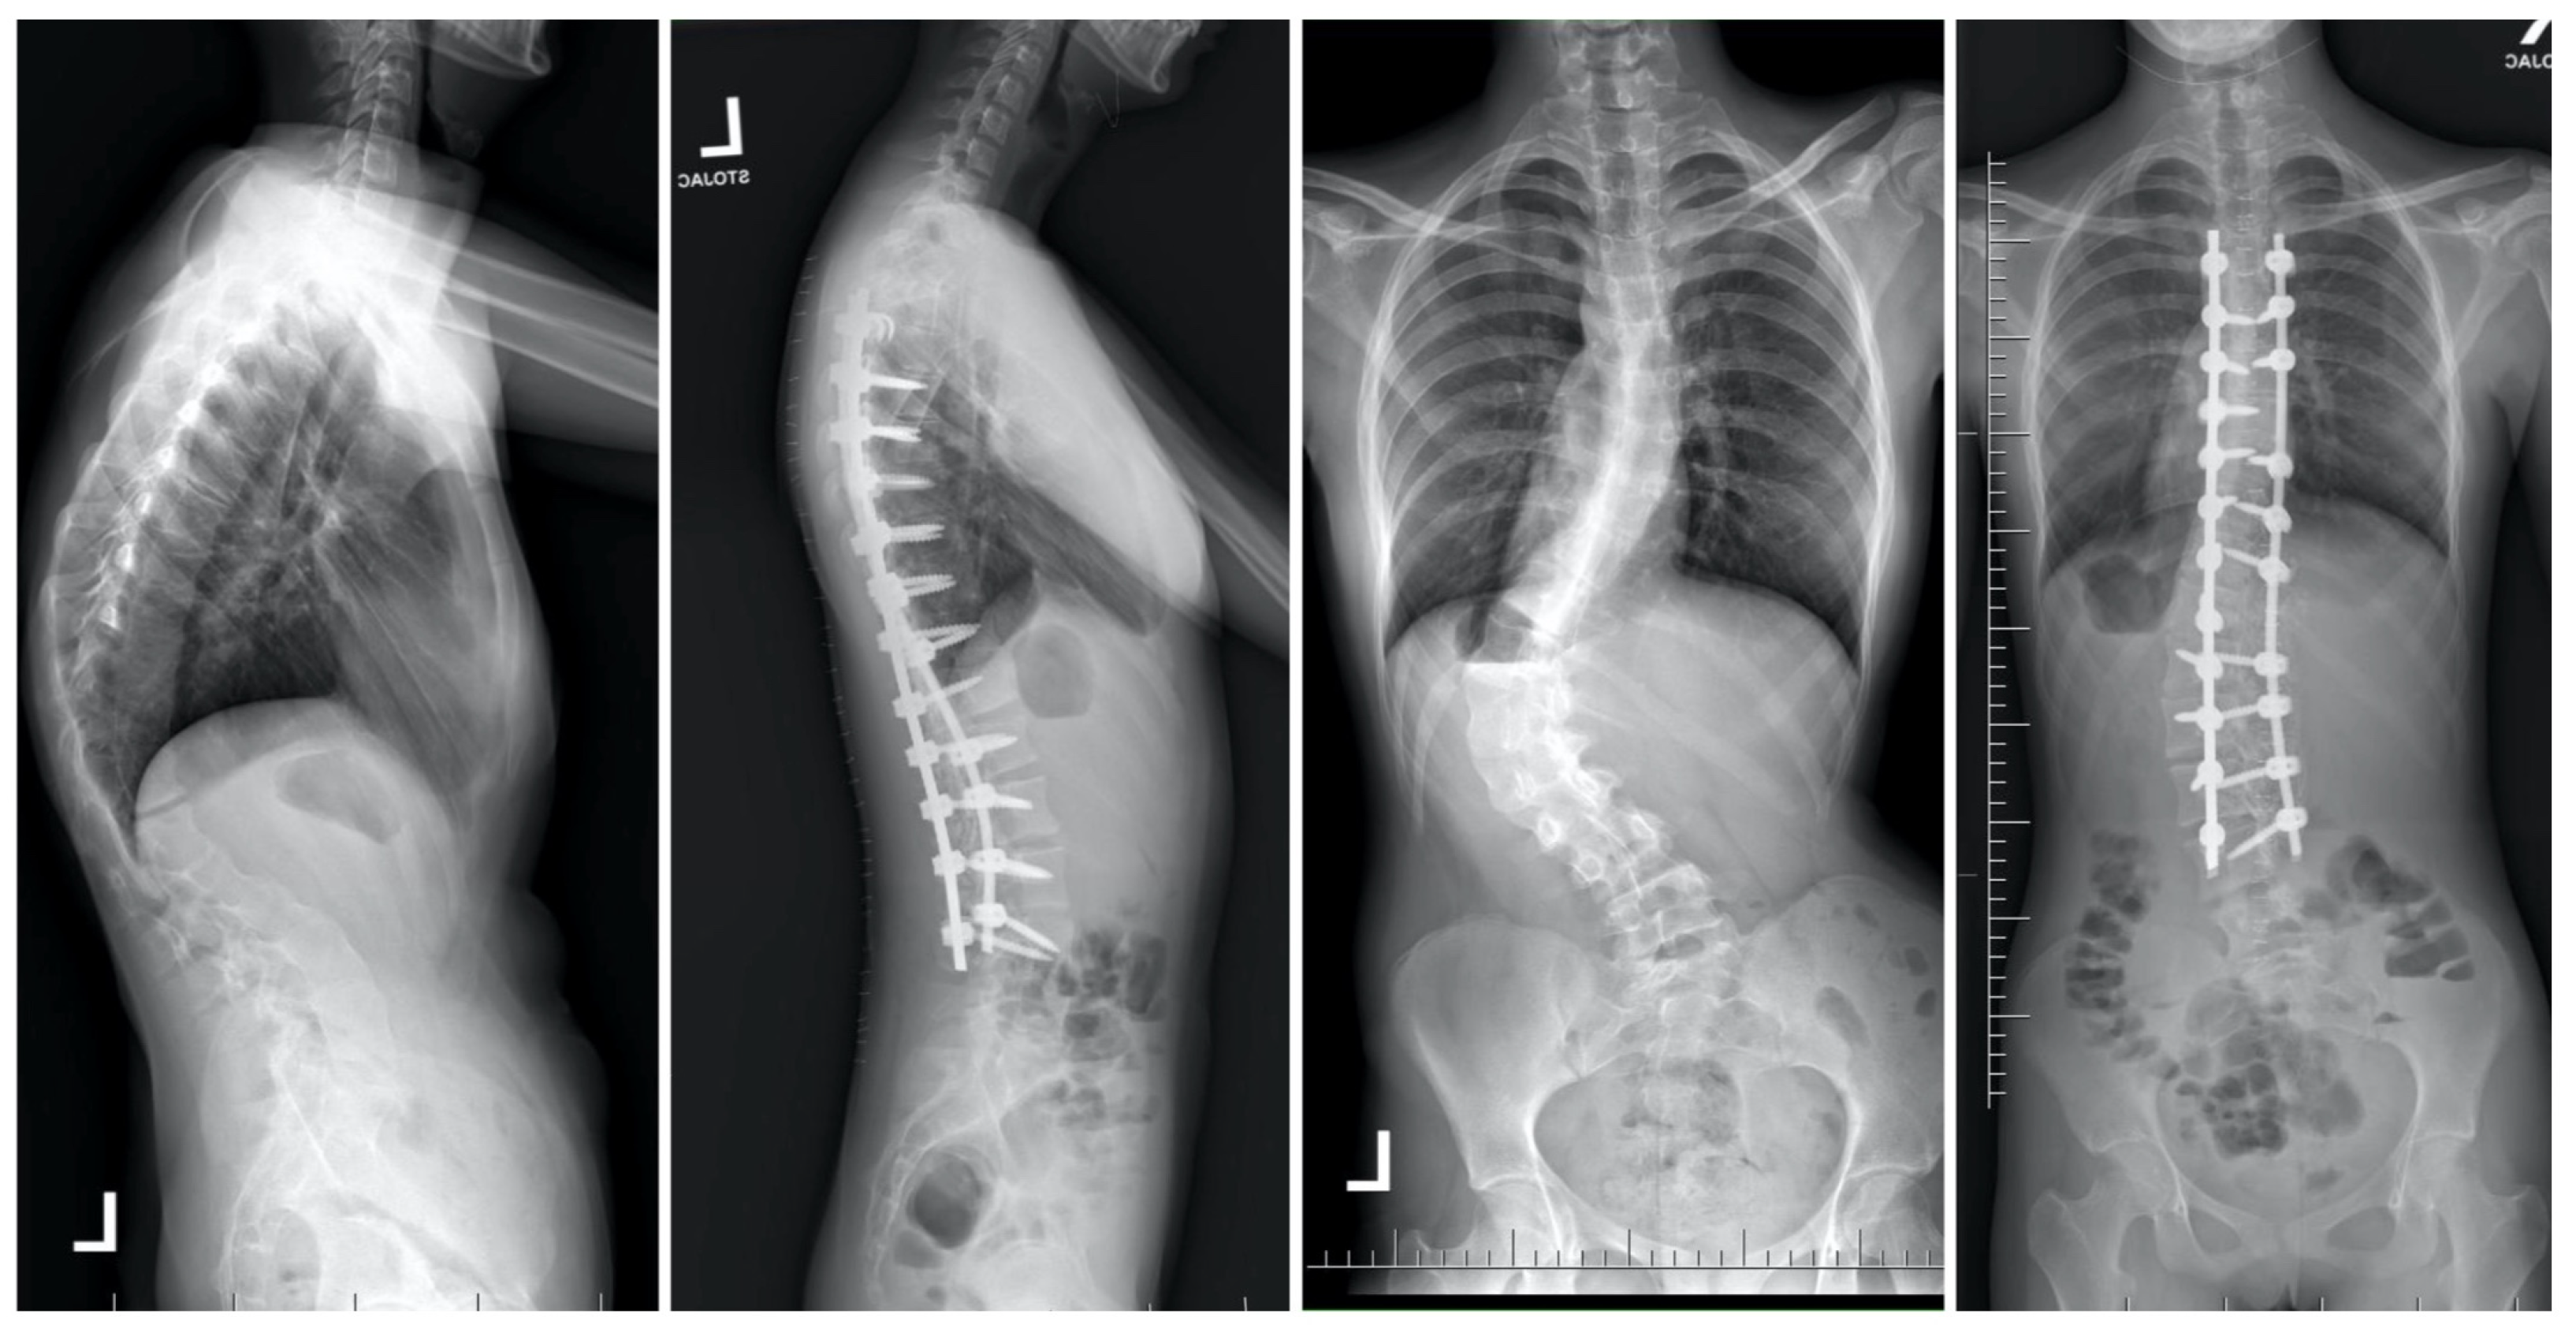

- Grabala, P.; Galgano, M.A.; Grabala, M.; Buchowski, J.M. Radiological and Pulmonary Results of Surgical Treatment of Severe Idiopathic Scoliosis Using Preoperative Halo Gravity Traction Compared with Less Invasive Temporary Internal Distraction in Staged Surgery in Adolescents. J. Clin. Med. 2024, 13, 2875. [Google Scholar] [CrossRef] [PubMed]

- Grabala, P.; Helenius, I.J.; Buchowski, J.M.; Shah, S.A. The Efficacy of a Posterior Approach to Surgical Correction for Neglected Idiopathic Scoliosis: A Comparative Analysis According to Health-Related Quality of Life, Pulmonary Function, Back Pain and Sexual Function. Children 2023, 10, 299. [Google Scholar] [CrossRef] [PubMed]

- Grabala, P.; Chamberlin, K.; Grabala, M.; Galgano, M.A.; Helenius, I.J. No Benefits in Using Magnetically Controlled Growing Rod as Temporary Internal Distraction Device in Staged Surgical Procedure for Management of Severe and Neglected Scoliosis in Adolescents. J. Clin. Med. 2023, 12, 5352. [Google Scholar] [CrossRef] [PubMed]

- Hu, H.M.; Hui, H.; Zhang, H.P.; Huang, D.G.; Liu, Z.K.; Zhao, Y.T.; He, S.M.; Zhang, X.F.; He, B.R.; Hao, D.J. The impact of posterior temporary internal distraction on stepwise corrective surgery for extremely severe and rigid scoliosis greater than 130°. Eur. Spine J. 2016, 25, 557–568. [Google Scholar] [CrossRef]

- Di Silvestre, M.; Zanirato, A.; Greggi, T.; Scarale, A.; Formica, M.; Vallerga, D.; Legrenzi, S.; Felli, L. Severe adolescent idiopathic scoliosis: Posterior staged correction using a temporary magnetically-controlled growing rod. Eur. Spine J. 2020, 29, 2046–2053. [Google Scholar] [CrossRef] [PubMed]